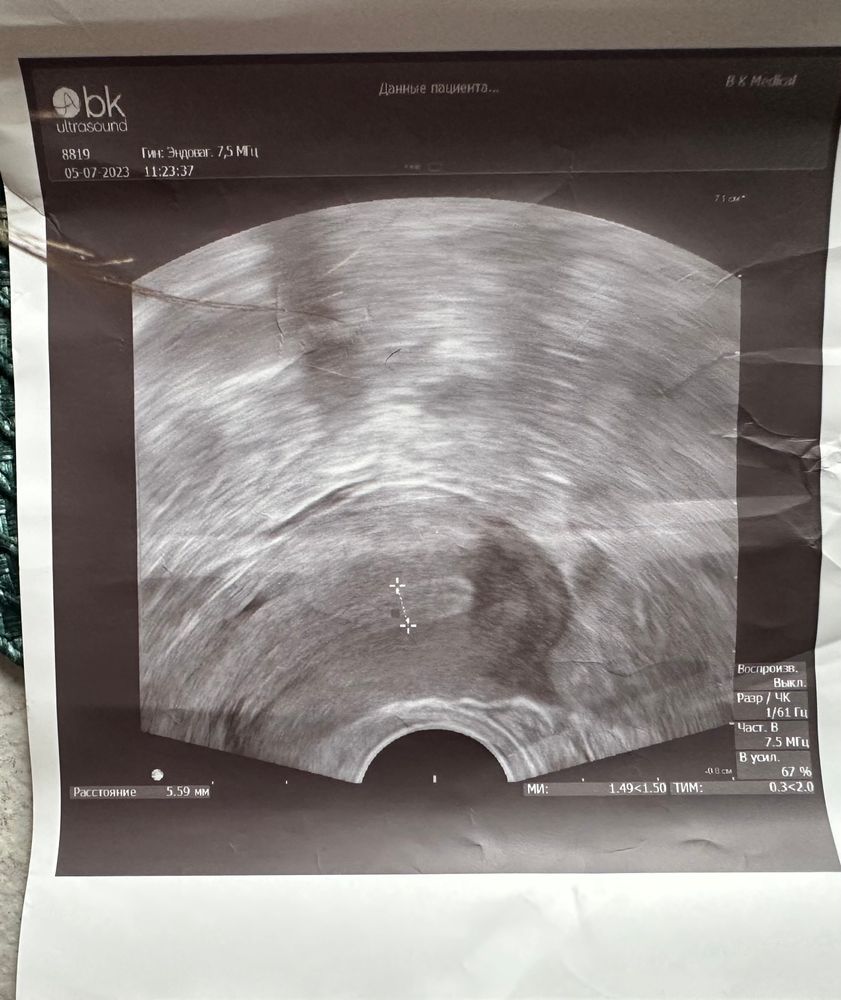

девушки,сегодня 13 дц в крио,была на узи,сказала эндометрий не очень по мм,но красивый.

Сказала три разных толщины,прямо и растянуть если сильно.

итог: 5,59 мм; 7,53мм; 6,86мм

Так вот какой верный то?Как понимать если надежда,что дорастет до 8мм хотя бы?Я так и не поняла.

фото прикрепляю,все за один сеанс